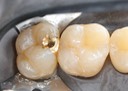

Joe Cha #18 pre-op

Joe Cha #18 composite removal